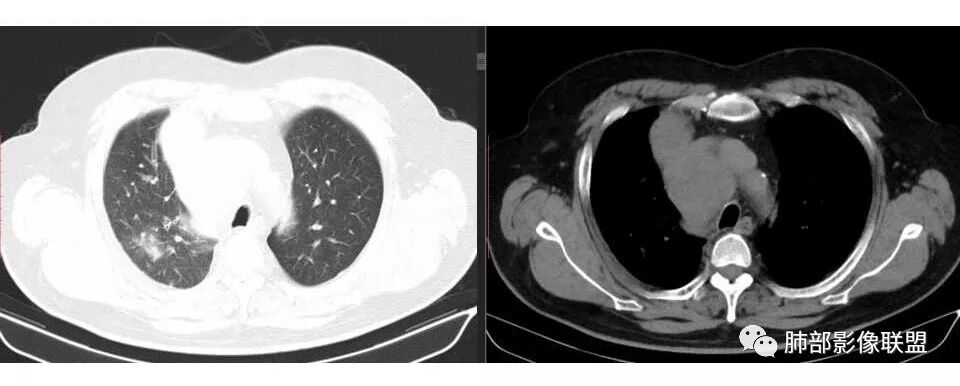

波波: 纵隔内多发肿大淋巴结,考虑小细胞肺癌,右上肺磨玻璃结节,考虑腺癌。

红日东升: 男性,有吸烟史,右肺上叶斑片,周围少于小叶间隔增厚,娘小崽大,冰冻右侧肺门、冰冻纵隔,符合恶性,侵袭性强癌淋轻,考虑小细胞可能,每年都参加体检但筛不出来的更倾向小细胞。

水晶石头: 患者中老年男性,以四肢乏力为症状表现,有吸烟史。胸部CT:右肺上叶不规则结节,周围见磨玻璃影,小叶间隔增厚。同侧纵膈明显淋巴结肿大。综合考虑恶性。存在小病灶大转移,冰冻纵隔,且有内分泌症状,首先小细胞癌可能大。监测排外淋巴瘤。

我支持肺癌,每年体检没发现,提示进展迅速,没看到肺内大病灶,吸烟,支持小细胞癌可能

宇宙星空: 支持南大的分析,简单总结为:冰冻纵隔,娘小崽大,右肺小结节,支持小细胞

结果:小细胞肺癌

1.右肺上叶不规则结节影,右肺门及纵隔多结节并形成巨大块影,密度均匀,沿途支气管明显狭窄。

原发灶小或隐匿,肺门纵隔淋巴结异常增大,所谓“娘小崽大”常见于肺小细胞癌!

2.右肺小叶间隔增厚伴微小结节,提示癌性淋巴管炎。

3.注意患者年年体检未见明显异常!

一年之内,甚至几个月内出现的肺部肿块,也几乎将鳞癌、腺癌、类癌、肉瘤等肺原发肿瘤彻底排除在外!